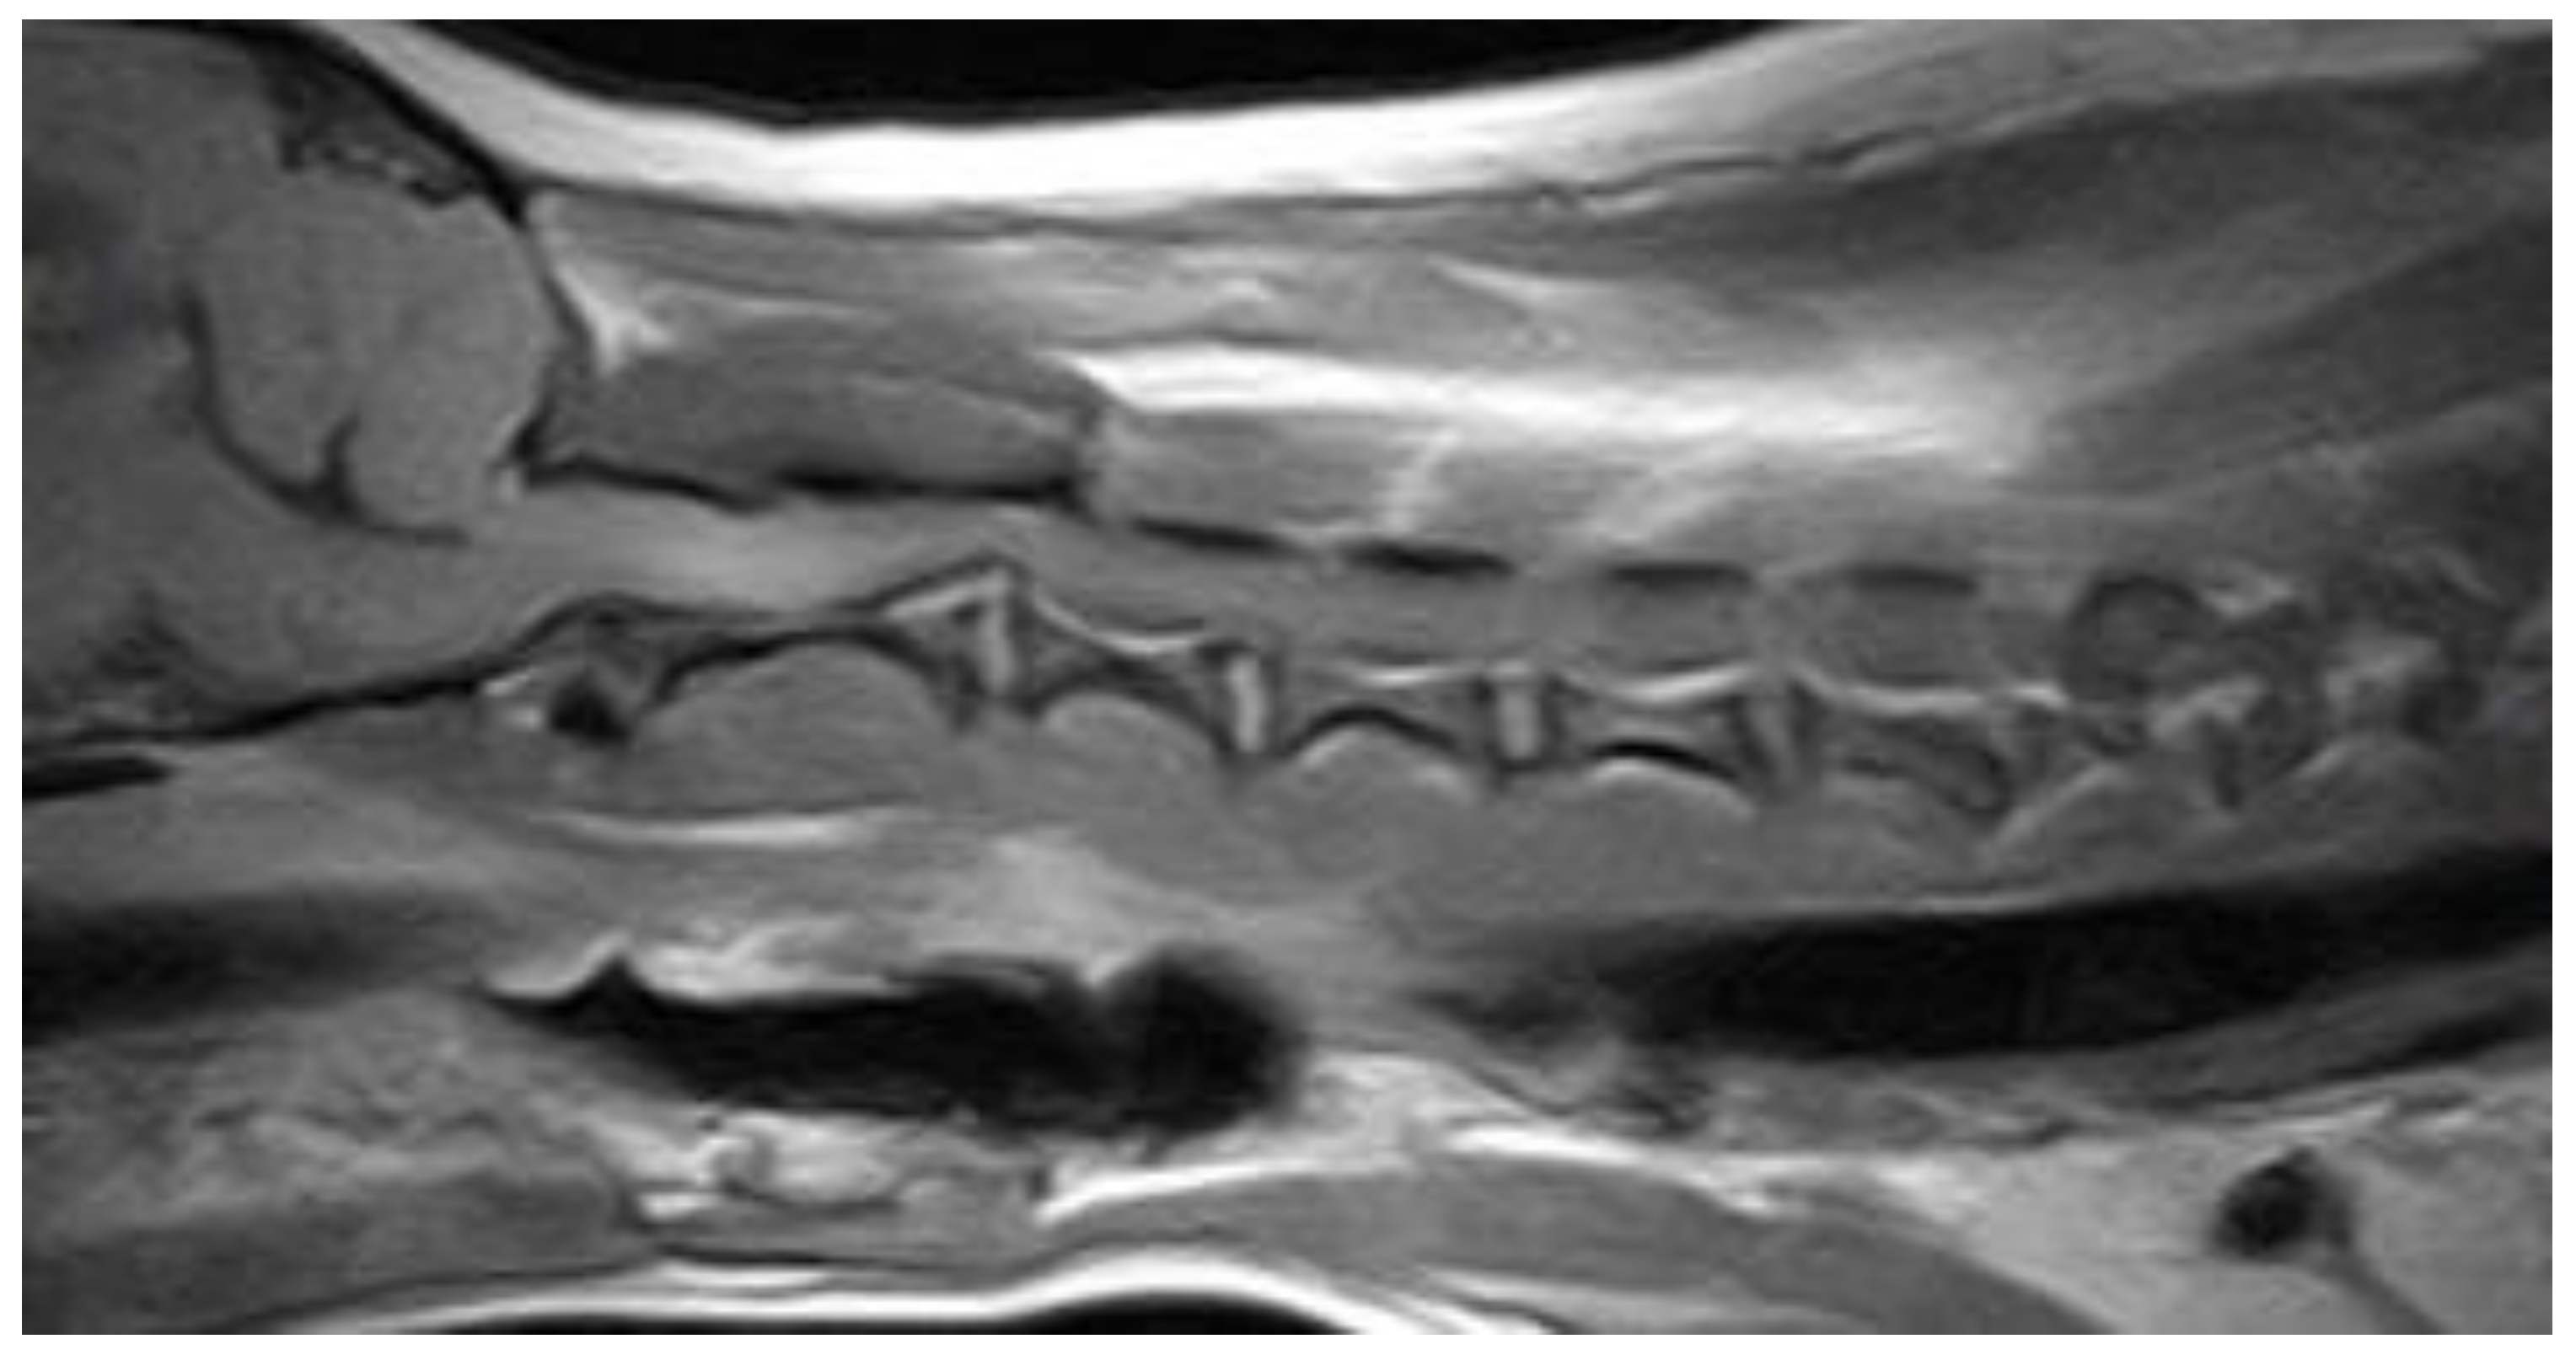

3.2. Diagnostic Imaging